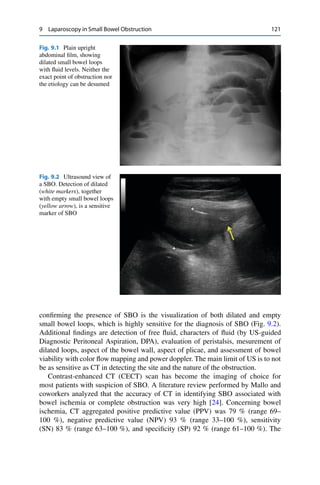

212 C. Rossiet al. 15.3.2.3 Disadvantages • Use of ionizing radiations 15.3.3 US • First imaging examination in suspected acute appendicitis, particularly in young adults and females • High safety and accuracy (lower than CT) [15] • Graded-compression US allows successful examination of a patient who may have peritoneal irritation [15] • Follow-up, in cases of nonsurgical right low pain [16] 15.3.3.1 US Findings • Aperistaltic, noncompressible, dilated appendix • US-McBurney’s sign • Appendicolith • Distinct appendiceal wall layers • Hyperechogenic pericaecal fat [16] • Periappendiceal fluid • Target appearance (axial section) • Appendiceal abscess [16] 15.3.3.2 Advantages • Differential diagnosis with gynecologic disorders • Initial imaging approach especially in children, young people and women of childbearing age [15] • Available • Repeatable • Non-invasiveness • Fast and cheap • Follow-up 15.3.3.3 Disadvantages • Operator dependent • Obese patients • Difficult detection of the appendix in atypical sites 15.3.4 Differential Diagnosis • Gynecologic conditions

• 222.

15 Imaging inEmergency Surgery 213 15.4 Gynecologic Disorders 15.4.1 Rationale • Identify causes of gynecological emergencies [17, 18] • Differentiate surgical from non surgical gynecological emergencies • Differential diagnosis with alternative causes of pelvic pain 15.4.2 US First technique used for acute gynecologic emergencies 15.4.2.1 US Findings • Free intrapelvic fluid • Uterine echogenicity and enlargement • Ovaries enlargement and echogenicity with multiple peripheric follicles • Liquid or solid masses • Ovaries displaced from its location with torsion of ovarian vessels [19] • Hemorrhagic ovarian cyst or hemorrhagic corpus luteum 15.4.2.2 Advantages • Provides an overview of uterus and ovaries • Ability to evaluate the relationship of uterus and ovaries with the adjacent organs • Possibility to use PD analysis to evaluate vascularization 15.4.2.3 Disadvantages • Low spatial resolution because of deep position of genital organs • Limited in women with abundant subcutaneous fat 15.4.3 Endovaginal US It requires dedicated intracavitary transducers; technique of choice for acute gyne- cologic emergencies [20]. 15.4.3.1 EVUS Findings • Optimal visualization of endometrium and myometrium • Size and location of ectopic pregnancy [21] • Hemorrhagic ovarian cyst or hemorrhagic corpus luteum • Presence of complications of PID such as tubo-ovaric abscess

• 223.

214 C. Rossiet al. 15.4.3.2 Advantages • Ability to perform a survey in obese women or with abdominal scars • High spatial resolution • High sensitivity for visualization of internal cavity 15.4.3.3 Disadvantages • Changes of endometrium with ormonal phases • May be difficult to differentiate benignant from malignant pathologies 15.4.4 MRI MRI is a second technique used: • To confirm or exclude US diagnosis • To evaluate complications 15.4.4.1 MRI Findings • Enlargement of uterus with alterations of signal • Identification of endometrioma and its rupture [22] • Hemorrhagic cyst associated with hemoperitoneum such as breaking of hemor- rhagic corpus luteum, or ovarian cyst • Characterization of masses such as liquid, solid, or mixed • Differential diagnosis between acute from chronic bleeding • Characterization of masses of pelvic inflammatory disease and its complications, such as tubo-ovaric abscess 15.4.4.2 Advantages • High specificity for characterization and differential diagnosis of adnexial masses • Allows a detailed anatomy • High panoramicity with possibility to individuate extra-pelvic pathologies caus- ing acute pelvic pain 15.4.4.3 Disadvantages • Long scanning time • Lower sensitivity than EVUS for visualization of internal cavity 15.5 Nonspecific Abdominal Pain 15.5.1 Rationale • To rule out the cause of nonspecific pain • To differentiate medical from surgical diseases • To avoid unnecessary laparotomies

• 224.

15 Imaging inEmergency Surgery 215 15.5.2 X-Ray Abdomen X-ray abdomen is the first imaging technique [23]; 15.5.2.1 X-Ray Findings • Signs of pneumoperitoneum; • Air-fluid levels, intestinal morphological changes, and behaviors; • Signs of small- and large-bowel obstruction (LBO) or Ogilvie’s syndrome • Fecal stasis. 15.5.2.2 Advantages • Provides an overview of abdominal cavity 15.5.2.3 Disadvantages • Serial plain films help understand interstinal behaviours • Low sensitivity to identify cause 15.5.3 CECT CECT may provide additional information compared to plain film [24, 25] 15.5.3.1 CECT Findings • May identify medical and surgical causes of abdominal pain • To evaluate the enhancement of solid organ and hollow viscera • To assess abdominal vessels • To assess presence and characterization of masses 15.5.3.2 Advantages • May identify both medical and surgical causes of abdominal pain [26] • High prognostic negative value [27] 15.5.3.3 Disadvantages • Use of ionizing radiations 15.6 Perforated Gastro-duodenal Ulcer 15.6.1 Rationale • Evidence of free intraperitoneal air • Definition of location of perforation

• 225.

216 C. Rossiet al. 15.6.2 X-Ray Abdomen First imaging exam. For positivity of exam, 1–2 ml of free gas are sufficient. At least 3 projections are needed: • Postero-anterior and latero-lateral in orthostatism • Postero-anterior in left lateral decubitus • Anterior-posterior in supine decubitus 15.6.2.1 X-Ray Findings • Free gas • Presence of free air in perihepatic, perisplenic, along the course of falciform ligament or round ligament, or in Morrison space is indicative of perforation of gastroduodenal ulcera [28] 15.6.2.2 Advantages • Fast and cheap • Repeatable • Performed also in supine patients 15.6.2.3 Disadvantages • Use of ionizing radiations 15.6.3 CT Most sensitivity method to research free gas [29, 30]. 15.6.3.1 CT Findings • Free air intraperitoneal • Associated signs of paralitic ileus (horizontal loops, air-fluid levels) • Spreading extraluminal contrast medium (rare, need oral contrast administration) • Discontinuity and thickening intestinal wall (rare) • Free intraperitoneal fluid 15.6.3.2 Advantages • Sensitivity of 99 % in identify pneumoperitoneum • It is able to recognize also small gas bubbles not visible to X-Ray abdomen • Can recognize the site of perforation [31, 32] 15.6.3.3 Disadvantages • Initial CT study may be negative for free air (covered perforation).

• 226.

15 Imaging inEmergency Surgery 217 15.7 Large-Bowel Obstruction 15.7.1 Rationale • To rule out LBO • Identification of the cause • Severity of LBO and possible complications • Differential diagnosis 15.7.2 X-Ray Abdomen • It is the first imaging study in patient suspected of having LBO • two views at least in critical patient (supine position Antero-Posterior and Lateral views) • When possible in both dependent (supine and prone) and nondependent (upright decubitus) • The sensitivity of abdominal radiography for the detection of LBO is 84 %, and the specificity is only 72 % as a result of difficult to distinguish between obstruction and colonic pseudo-obstruction [33, 34] 15.7.2.1 X-Ray Findings • Colon may be glossily dilated proximal to the site of obstruction “transition zone” with paucity or absence of gas distal to the obstruction site [35] • Air-fluid levels • Pneumatosis (unusual and difficult to detect) • Portal venous gas (unusual and difficult to detect) • Pneumoperitoneum • Abnormal location of colonic segments (volvulus) 15.7.3 CT • CECT is the gold standard for the evaluation of LBO • Well-tolerated, rapid imaging study • High sensitivity (96 %) and a specificity (93 %) [36, 37] 15.7.3.1 CT Findings • Dilated large bowel proximal to the transition point and collapsed bowel distal to the site of obstruction [38] Colon Carcinoma LBO – Asymmetric and short-segment wall thickening